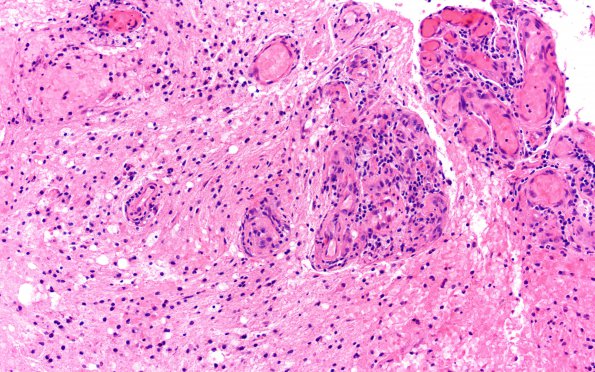

Washington University Experience | MYELIN (NON-IMMUNE MEDIATED) | Retinal Vasculopathy with Cerebral Leukoencephalopathy (RVCL, TREX1 Mutation) | 15B3 CRV (Case 15) A3 H&E 20X 1

The vasculature is collected in proliferative groups with prominent endothelial cells and vessels with mildly thickened collagenous walls. The intervening parenchyma is pale with numerous macrophages and proliferating astrocytes. (H&E)